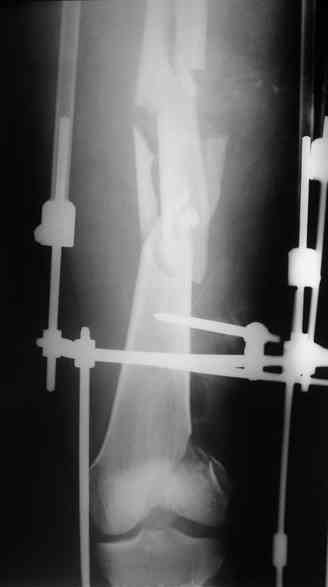

После окончательного заживления раны снять аппарат наложить вытяжение дней на 5-7, посмотреть как ведут себя раны от стержней. Одномоментное снятие аппрата с забиванием гвоздя чревато, сколько, кстати он уже стоит?

Выждав, немного, сделал бы антеградный интрамедуллярный остеосинтез. Насчет того, чтобы винты, фиксирующие мыщелок являлись одновременно блокирующими не согласен - далековато гвоздь забивать придется. Хотя не уверен на 100%

Это интуитивные опасения, или есть конкретный клинический материал, который показал высокий уровень осложнений при одномоментной смене наружного фиксатора на стержень?

Если гноя у спиц-стержней нет даже при сроке в аппарате 6-12 мес., смена по крайней мере на бесканальный титановый штифт относительно

безопасна, глубокая инфекция по нашим данным (~150 таких операций) около 4%.